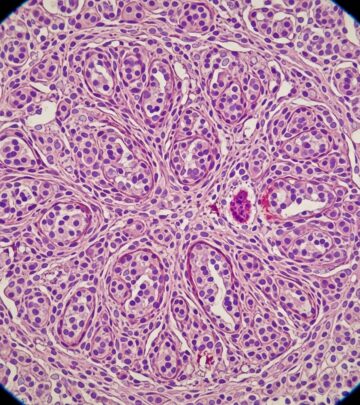

Fibrofolliculomas in Birt-Hogg-Dubé Syndrome Images